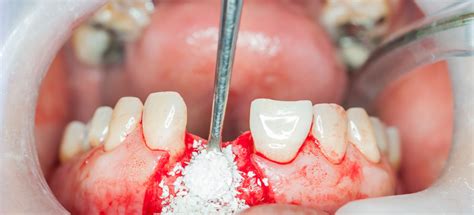

Un injerto óseo es como espaciar un agujero, hecho de partículas de hueso que entran en el agujero donde estaba el diente y está cubierto por una membrana estéril. El cuerpo disuelve las partículas de hueso y las integra en el propio hueso de la persona. Es un mantenedor de espacio y un andamio. El cuerpo quiere curar una herida colapsándola, así que al espaciar ese agujero, lo llena.

Típicamente toma alrededor de medio CC, así que muy, muy poco.

La membrana - que es ese vendaje estéril - sostiene las partículas de hueso en la mandíbula. Si el paciente manipula el área y hace que la membrana se levante, entonces sí, las partículas pueden salir.